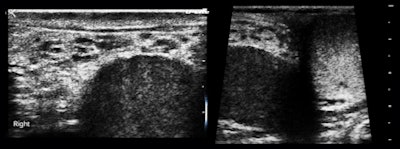

One of the first cases I was asked to see was a 23-year-old man with painless swelling of the right half of the scrotum for the previous five years. The patient wanted to know if this might affect fertility (figure 2).

Our impression was fibrous pseudotumor of the tunica vaginalis, which is a reasonably rare occurrence. There were no additional findings supportive of filariasis or schistosomiasis, which are even rarer with unilateral scrotal presentations. This case illustrates the challenge for the examiner to be familiar with the area he or she is imaging, or to know how to go from image findings to the proper reference source immediately.